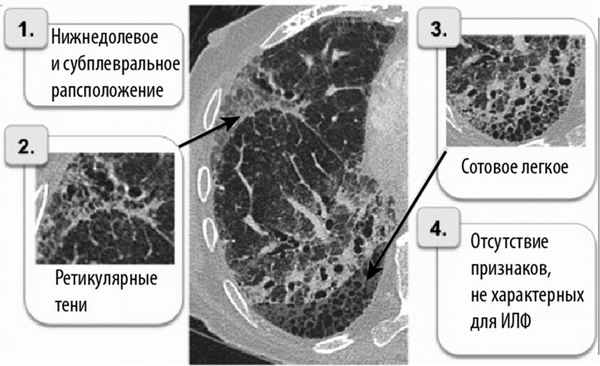

— Для выделения ИФЛ из группы других идиопатических ИБЛ основным ориентиром служат результаты КТ легких высокого разрешения [4] (рис. 2).

Рис. 2. Главные компьютерно-томографические признаки ИФЛ.

В соответствии с диагностическими признаками ИФЛ по данным КТ выделяют 3 категории вероятности наличия у больного ИФЛ [4]:

— субплевральное расположение в нижних долях;

— сотовое легкое ± тракционные бронхоэктазы;

— отсутствие признаков несоответствия.